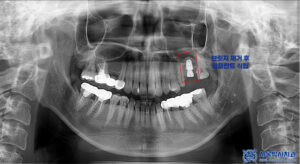

이에 신흥동치과 서울박사에서는

위쪽 브릿지를 모두 제거하고,

지대치는 크라운으로 다시 보철하며

인공치가 있던 부위는

임플란트 식립을 진행하기로 했습니다.

아래쪽 보철 역시 제거 후 상태에 맞춰

재보철을 진행하는

계획으로 안내드렸습니다.

먼저 왼쪽 위 치아 부위의

기존 보철물을 제거한 뒤

임플란트 식립을 진행했습니다.

치아가 오랫동안 없는 상태로 유지되다 보니

잇몸뼈가 일부 흡수되어

양이 부족한 상황이었습니다.

이에 따라 부족한 뼈를 보강하기 위해

뼈이식을 함께 진행하며

임플란트를 식립했습니다.